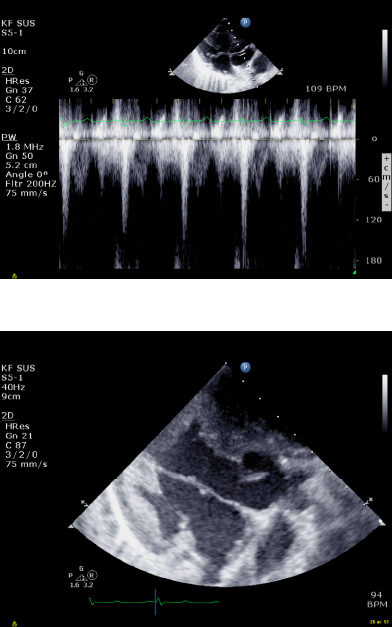

by the echocardiography images. Moreover, stroke

volume could be calculated from pulsed Doppler

recordings obtained in the left ventricular outflow

tract (figure 2). The results from the myectomy

Figure 2: Shows Doppler recordings.